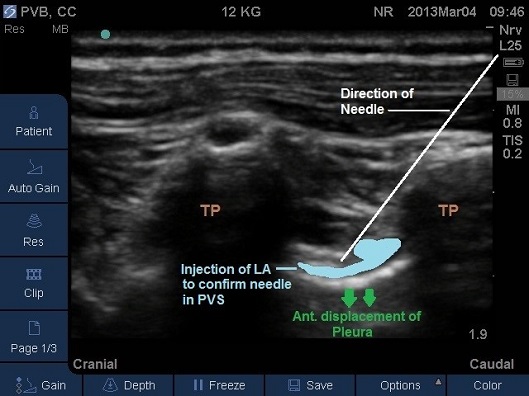

- Correct placement of the needle in the thoracic Paravertebral space should be confirmed by the anterior displacement of pleural upon injection of a small bolus of saline or local anaesthetic (Fig 13-16).

- Once confirmed the required volume of local anaesthetic should be injected.

Fig 14. Paravertebral space entered by needle, pleura displaced anteriorly by local anaesthetic.

Fig 15. Paravertebral space entered by needle, pleura displaced anteriorly by local anaesthetic. TP –transverse process. Local anaesthetic spread marked in light blue